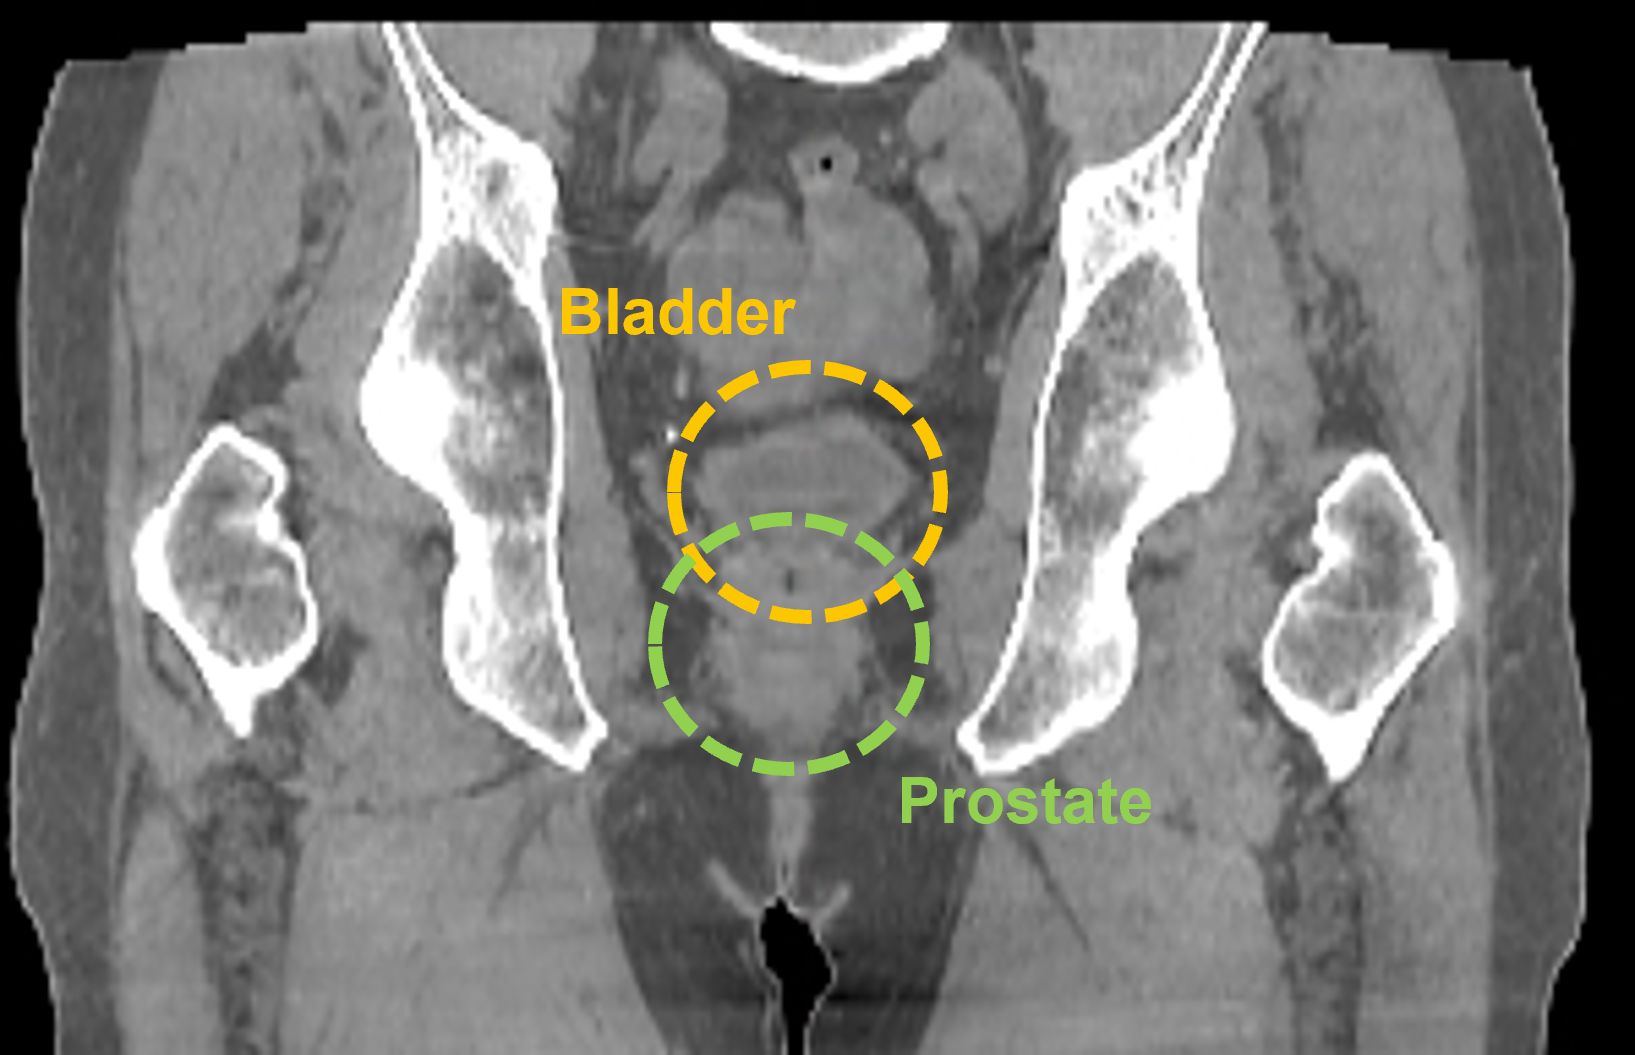

Prostate

In this prostate case, the larger FOV provided by the HyperSight image, taken using a Varian TrueBeam system, enables a clinician to see the entire treatment area including the lymphatic region, which may also require treatment. It also enables the clinician to visualize the relevant anatomy without acquiring multiple CBCT images.